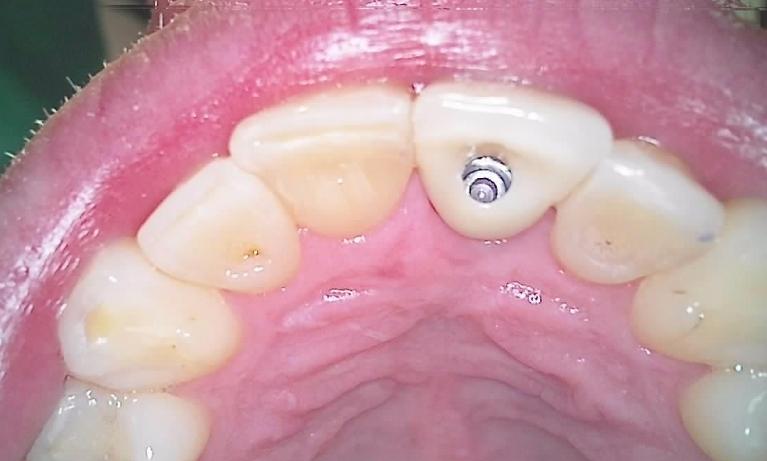

We take great pride in the services we perform in our office. We always try to not only meet your expectations, but we also try to exceed them. There are many types of services that we perform in our office, as well as others that we perform in coordination with highly skilled specialists. We have compiled a few examples of the treatments that we have performed. We are proud to say that these are the usual results our patients expect to see.

The photos are not retouched, nor are they taken by a professional photographer. These are just the routine treatment photos that we take and the results that we see every day. They are by no means a comprehensive catalog of the procedures that we perform. They are just a small sample of some of the results you can expect when you seek treatment in our office.